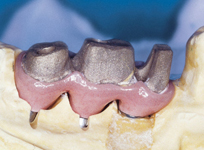

Protetické řešení může být pomocí můstku, který je kotvený na implantátech nebo pomocí jednotlivých korunek na implantátech.

V zásadě je možné do těchto můstků zařadit i přirozené zuby, zejména pokud je potřeba tyto zuby ošetřit proteticky - korunkami. Korunky nebo můstky mohou být na implantáty nacementovány nebo přišroubovány.

Pevné můstky – lepené nebo šroubované